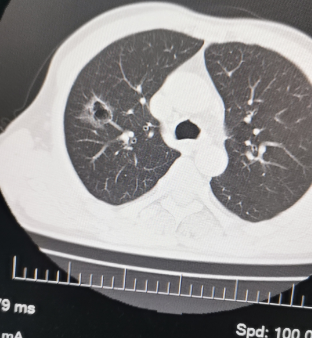

10、**男士,30岁

于2023年7月17日在邯郸仁泰南区体检,低剂量薄层CT扫描提示:右肺上叶磨玻璃结节,空洞结节,较大结节大小约30mm,考虑非良性结节。建议客户到综合医院专科进一步检查。2023年7月23日电话回访,客户已到北京协和医院复查, 进一步检查明确病变性质。2023年7月31日跟踪回访,客户已在北京协和医院手术治疗。